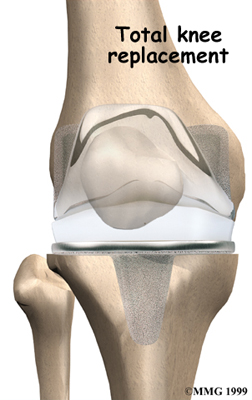

Artificial Knee Replacement

An artificial knee replacement is the ultimate solution for advanced knee OA.

Surgeons prefer not to put a new knee joint in patients younger than 60. This is because younger patients are generally more active and might put too much stress on the joint, causing it to loosen or even crack. A revision surgery to replace a damaged prosthesis is harder to do, has more possible complications, and is usually less successful than a first-time joint replacement surgery.

Related Document: FYZICAL North Hills Guide to Artificial Joint Replacement of the Knee